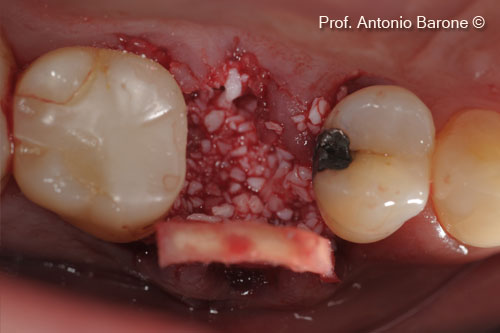

Hình ảnh lâm sàng mặt nhai của mảnh ghép xương ổ răng với chất nền mp3 và derma